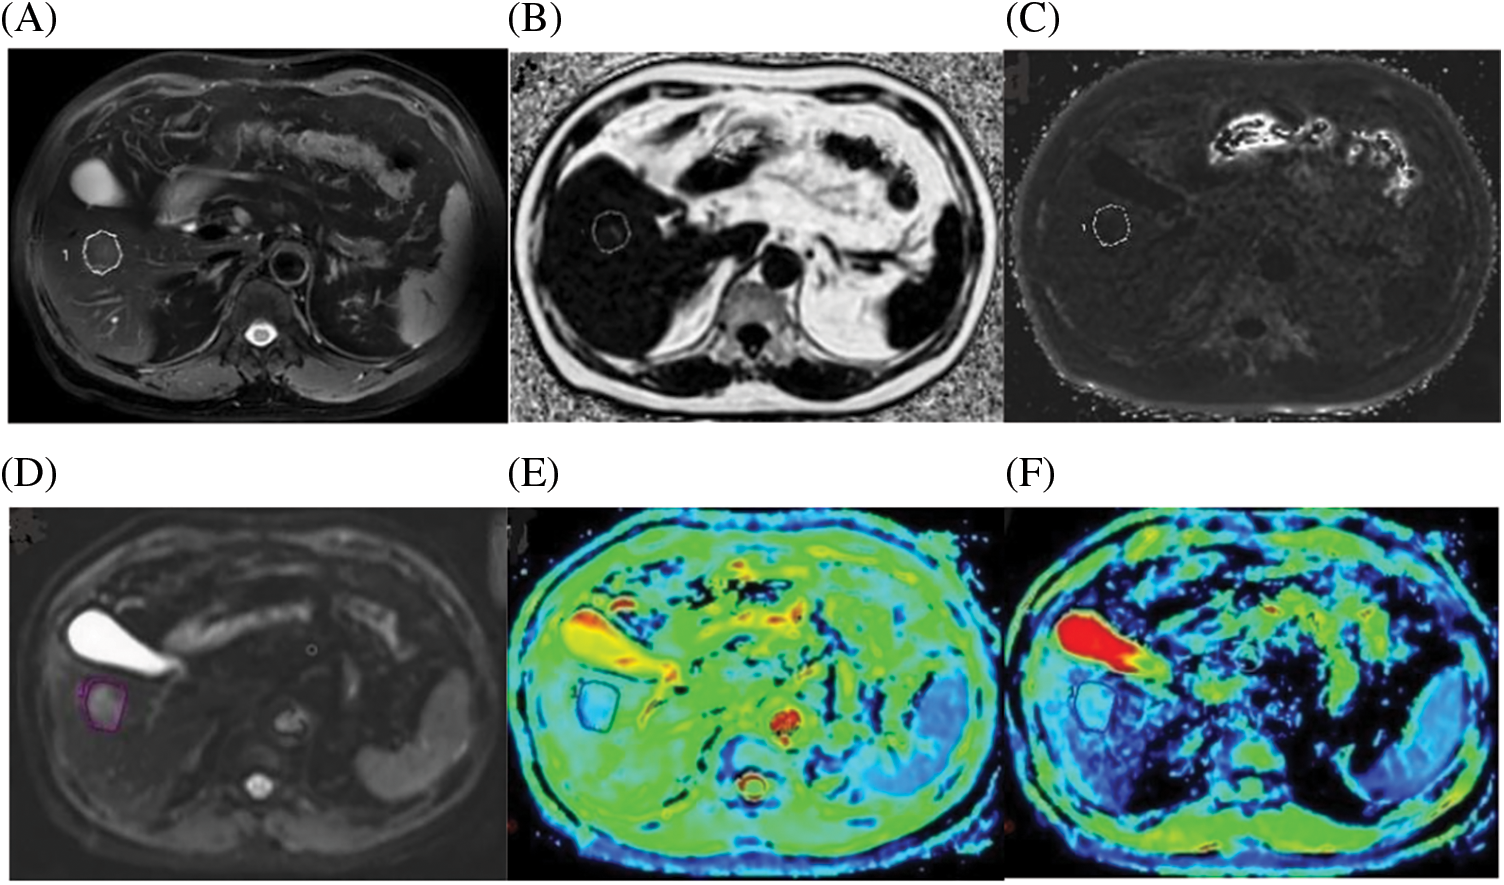

Figure 2: A case of a 72-year-old male with HCC confirmed by histopathology. (A) Axial fat-suppressed T2-weighted unenhanced image showing a freehand ROI. (B) Fat Fraction (FF) = 10.21%. (C) R2* relaxation rate = 21.56 Hz. (D) IVIM Diffusion-weighted image (b = 0 s/mm2), according to regular MRI sequences, shows a freehand ROI. (E) ADC = 1.042 A × 10−3 mm2/s. (F) D = 0.635 × 10−3 mm2/s